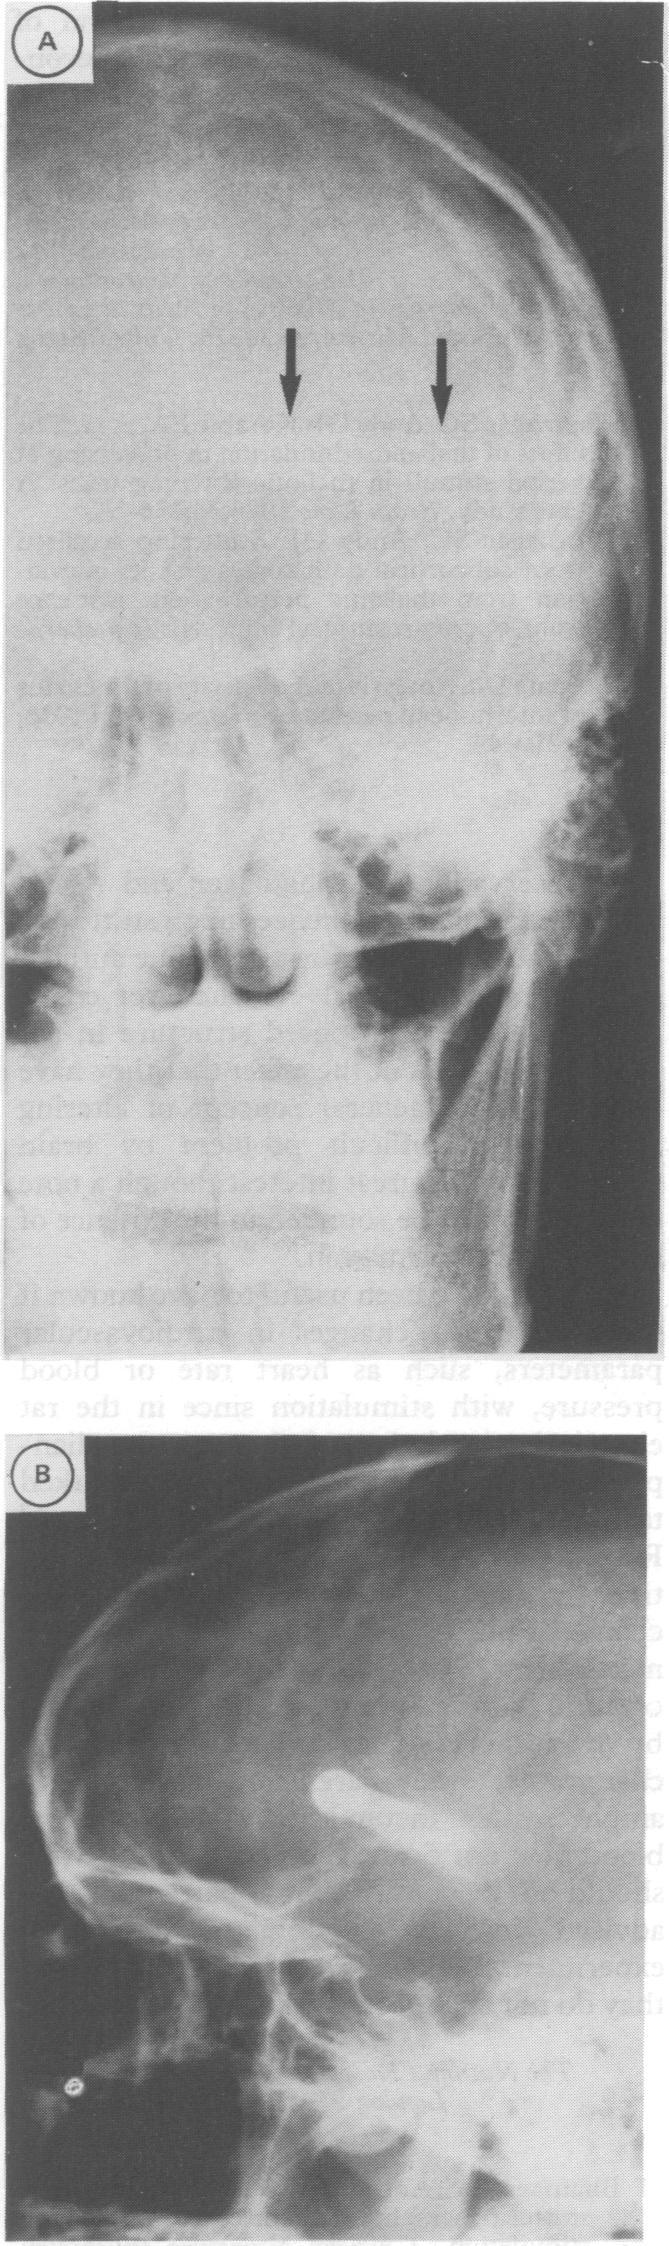

Atypical meningitis complicating a penetrating head injury.

J Neurol Neurosurg Psychiatry. 1991 Jan;54(1):92-3. doi: 10.1136/jnnp.54.1.92-a.

Atypical meningitis complicating a penetrating head injury.穿透性头部损伤并发非典型脑膜炎。